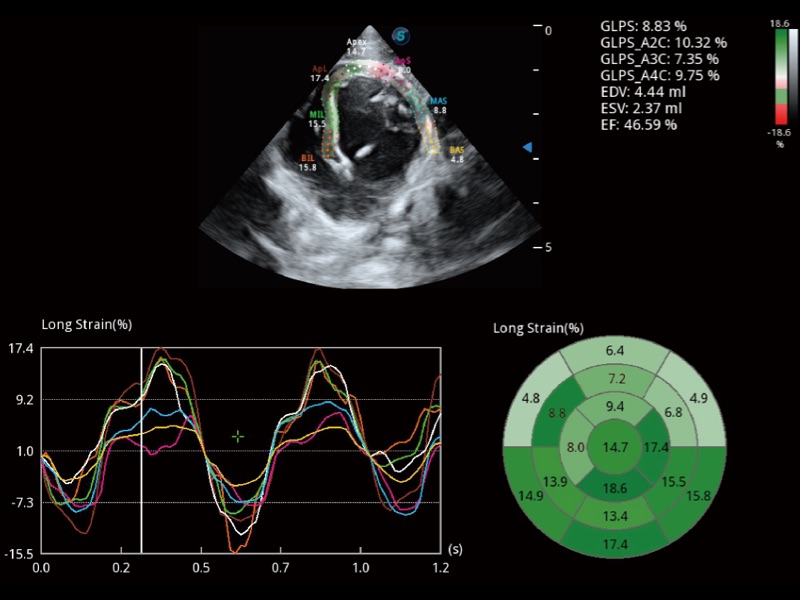

能够基于左心室壁追踪和辛普森法,自动计算射血分数,支持多个可移动点描迹,与手动测量相比,极大节省了动物医生的时间和精力。

具备多种协议可选,同时支持17阶段划分法和专业的SE报告。

当心脏测量结果超出正常范围时,可实时预警提示动物医生,减少疾病漏诊概率。